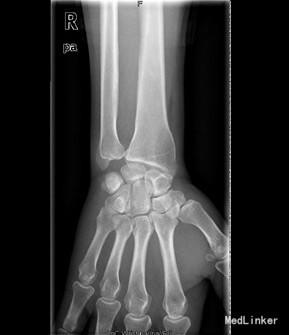

患者男,60岁,因“右腕部疼痛5月,右小指屈曲障碍20天”入院。入院前5月,患者无明显诱因情况下出现右侧腕部尺侧酸痛不适,未就诊治疗。左小指伸曲正常;入院前20天,患者出现右小指屈曲障碍,无小指指麻木,遂来我院治疗,门诊以“左小指深浅屈肌腱迟发性断裂”收入院。

查体:右侧小指伸直位,不能屈曲。右侧腕部尺侧可触及一质韧包块。右小指感觉正常,末梢循环正常。右小指不能主动屈曲掌指关节及中节、末节手指;伸指正常,余手指活动正常。 辅查:彩超:右腕包块处肌腱周围粘稠积液伴滑膜增厚。